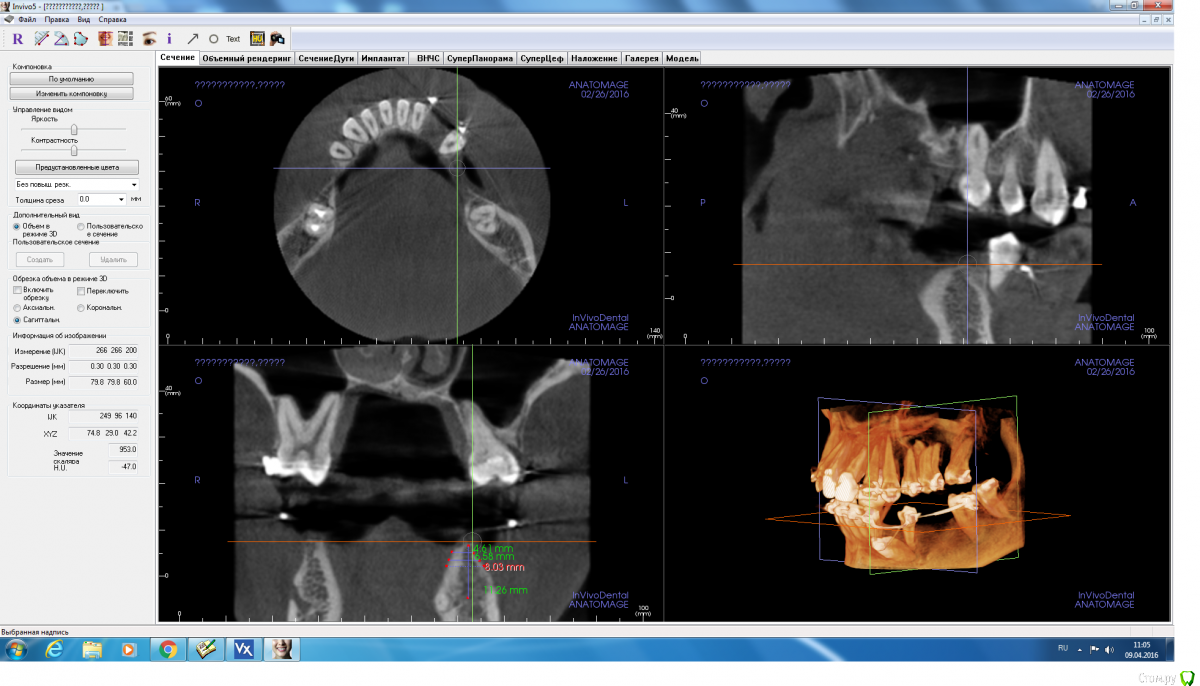

Fibez Опубликовано 8 апреля, 2016 Поделиться Опубликовано 8 апреля, 2016 Ред_бутлер, там же всего 10 мм от края гребня до канала? Куда заглубляться-то? Или ставить 3,5х8мм? Ссылка на комментарий

Aquarius Опубликовано 8 апреля, 2016 Поделиться Опубликовано 8 апреля, 2016 8,5 вполне себе рабочий размер Ссылка на комментарий

red_butler Опубликовано 8 апреля, 2016 Поделиться Опубликовано 8 апреля, 2016 Ред_бутлер, там же всего 10 мм от края гребня до канала? Куда заглубляться-то? Или ставить 3,5х8мм?С чего Вы взяли, конечно выставленные скрины полной информации не дают, но мне видятся 12-14 мм Ссылка на комментарий

adamskot Опубликовано 9 апреля, 2016 Автор Поделиться Опубликовано 9 апреля, 2016 Пойду на аутоблок, с ретромолярной области, чтобы восполнить потерю вестибулярно в позиции 35.В позиции 36 поставлю одновременнно через 4 мес с 35. Будет более бюджетно, нежели мембрана,ксено и скребок...Надеюсь, срезы сейчас удачны для обзора)) Ссылка на комментарий